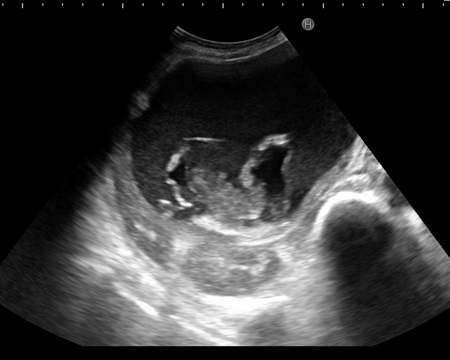

Kyste hydatique a grand

taille univesiculaire , ovalaire et aechogene avec

paroi visible de type 1 |

Kyste hydatique arrondie a

grand taille , aechogene avec image de decollement

de la membrane germinative interieure ( Type 2

) |